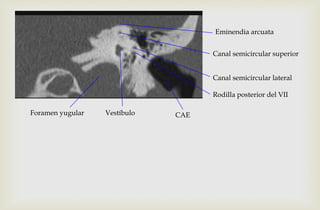

Eminendia arcuata

Canal semicircular superior

Vestíbulo

Canal semicircular lateral

Rodilla posterior del VII

CAEForamen yugular